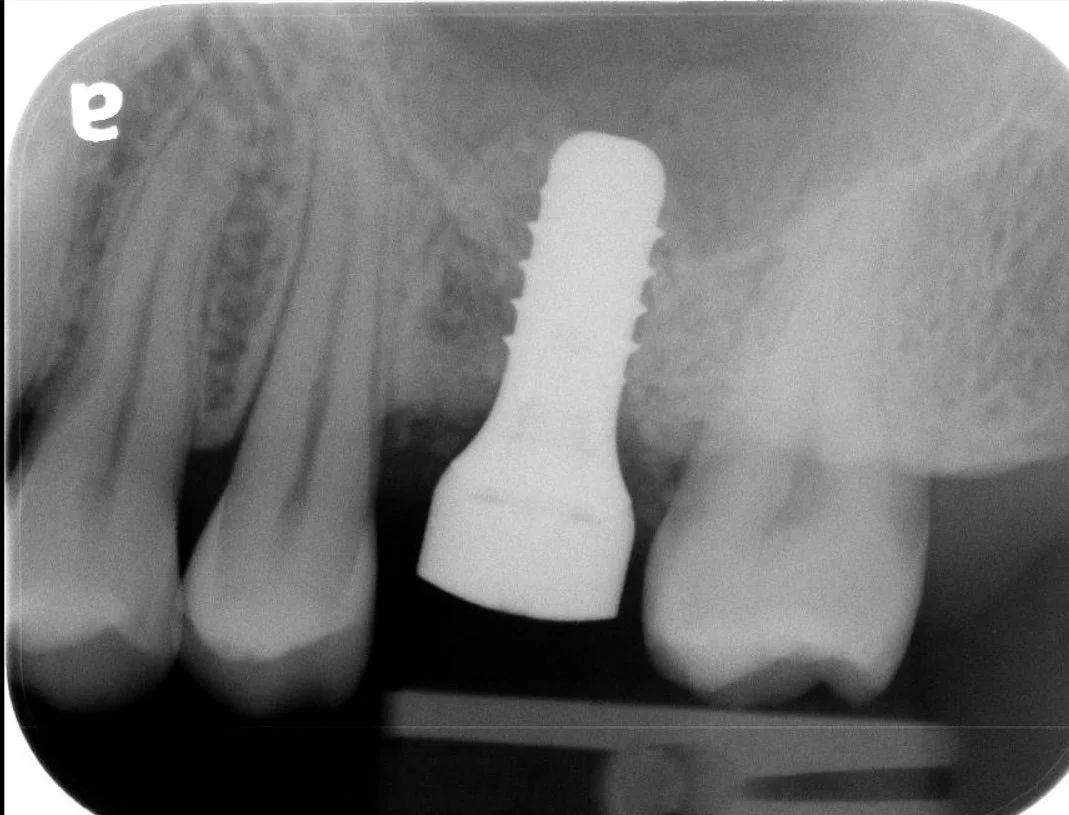

1. Single Tooth Restoration

The most common application for an implant is replacing a single missing tooth. Unlike a bridge, an implant does not require the "grinding down" of healthy adjacent teeth.

• The Component: A medical-grade titanium post acts as a synthetic root.

• The Benefit: It prevents the surrounding teeth from shifting and stimulates the jawbone to prevent bone loss.

• The Result: Once healed, your general dentist places a custom crown that looks, feels, and functions like a natural tooth.